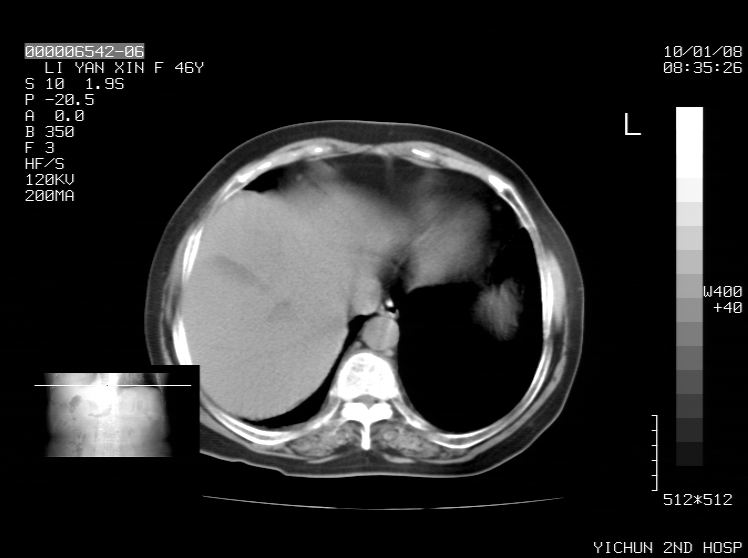

右侧膈膨升,胆囊壁厚,右侧肾脏缺如。病史?

右侧膈膨升,右肾脏切除术后

右侧膈膨升,肝内钙化灶,胆囊壁厚,右侧肾脏缺如。病史?

右膈膨出,肝脏变异,肝内钙化,右肾缺如,脾大。

右侧膈膨升,肝内胆管结石?

右侧肾脏缺如。病史?

右侧膈膨升,胆囊壁厚,右侧肾脏缺如,增强,腔静脉旁是否是移位肾

肝脏变异致膈升高,肝左叶肝内胆管结石.右肾萎缩,左肾代偿肥大.

胆囊ct未见确切异常,请结合b超。右侧肾窝未见确切肾脏影,右肾萎缩?异位?

右侧膈膨升,肝内钙化灶,胆囊壁厚,右肾萎缩或发育不良。